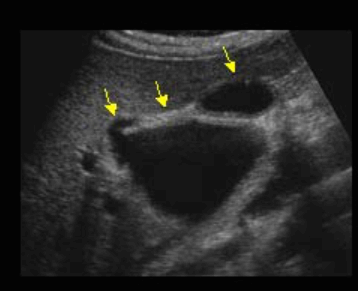

US finding

- 담관과 연결되는 많은 낭포가 있다.

- 담관 내 결석과 반사체가 보인다.